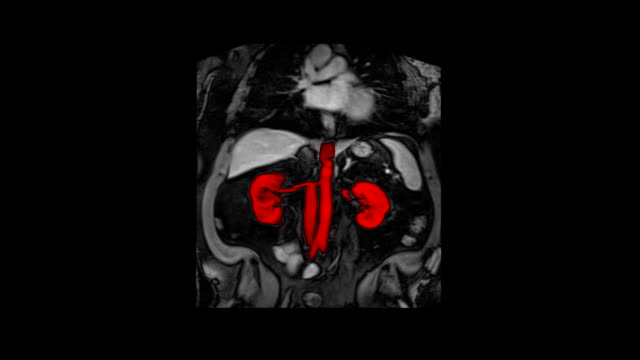

6. 허리 통증

신장은 양쪽 옆구리에 위치하기 때문에 신장에 문제가 생기면 허리 통증이 발생할 수 있습니다. 허리가 아플 때에는 신장 검사를 고려해야 합니다.